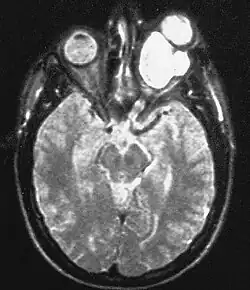

Den Großteil der bei Neurofibromatose Typ 1 auftretenden Gliome machen die im Bereich des Sehnervs (Nervus opticus) lokalisierten gutartigen pilozytischen Astrozytome aus, die bei dieser Lokalisation auch als Optikusgliome bezeichnet werden. Bei der Neurofibromatose Typ 1 treten Optikusgliome charakteristischerweise bilateral auf und betreffen so beide Sehnerven. Optikusgliome können bei Patienten mit Neurofibromatose Typ 1 einen über viele Jahre statischen Verlauf haben. Andere Gliome, die bei Neurofibromatose Typ 1 vermehrt auftreten, sind manche Astrozytome und das bösartige Glioblastom.

ZNS-Tumoren (zum Beispiel das Pilozytische Astrozytom bei NF 1 und das Schwannom bei NF 2) und neurologische Symptome treten als ernstzunehmende Probleme der Neurofibromatose auf. Vor allem Tumoren der Hirnnerven können chirurgische Interventionen notwendig machen. Akustikus- und Trigeminus-Neurinome, die vorwiegend bei NF 2 auftreten, verursachen besonders Hörverlust, aber auch Schmerzen. Ein Foramen-Jugulare-Syndrom und Hypoglossus-Tumoren bewirken entsprechende Symptome, ein Optikus-Gliom kann eine einseitige Blindheit und Tumoren der Spinalwurzeln können Lähmungen und Schmerzen verursachen. Darüber hinaus werden verschiedene neurologische Symptome beschrieben: Betroffene Kinder haben oft einen niedrigen IQ, eine ADS oder ADHS, Probleme mit der Selbstorganisation, Motorik-Schwächen sowohl fein- als auch grobmotorisch, dadurch Schulschwierigkeiten, eher selten eine Epilepsie und bei Hypothalamus-Hamartomen eine Pubertas Präcox. Bei Auftreten von epileptischen Anfällen bei Patienten mit einer Neurofibromatose, kann dies als Zeichen dafür gelten, dass sich ein Hirntumor entwickelt.